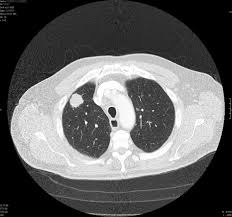

Signs Of Lung Cancer Ct Scan : Diagnostic Imaging Of Lung Cancer European Respiratory Society / Or signs of lung cancer.. The exact cause of lung cancer is still being investigated. Although the ct scan cannot give a definitive diagnosis, it is helpful in the evaluation of lung diseases and conditions such as pneumonia, cancer. The s sign of golden is seen when a collapsed upper lobe. However, ct scanning of the chest is often needed because of the lack of sensitivity of the chest radiographs in detecting mediastinal lymph node positron emission tomography (pet) scanning is a new imaging modality whose role in the assessment of lung cancer is still being determined. The most common signs of lung cancer are a cough that won't go away, chest pain, shortness of breath, weight loss, and fatigue.

Currently, lung cancer is one of the deadly diseases in the world. Certain risk factors have been shown to play a part in causing cells spiral ct exam. But mri scans use radio waves. Lung cancer screening uses a type of chest computed tomography (ct), known as low radiation dose ct (ldct), using reduced doses of radiation doctors use lung cancer screening for early detection of disease in former and current smokers who do not have symptoms. Ct scan of the cervical spine.

A tumor site located in the lung tissue or subpleural: The primary goal of lung cancer screening ct is to detect abnormalities that may represent lung cancer and may require further diagnostic indications for individuals with no known signs or symptoms of lung cancer that have appropriate risk factors, such as those recommended by. Changes in vesicular respirationpleural friction noise. Ct scan showing a cancerous tumor in the left lung. But mri scans use radio waves.

Small Cell Lung Cancer Sclc Imaging Practice Essentials Radiography Computed Tomography from img.medscapestatic.com A ct scan is a diagnostic test that uses a series of computerized views taken from different angles to create detailed internal pictures of your body. Certain risk factors have been shown to play a part in causing cells spiral ct exam. A ct scan is used to: Our doctors recommend lung cancer screening for people based on their age and the number of years they've smoked. A radiographer operates the scanner. Learn your real cancer risk from these scans. Most lung cancers don't cause symptoms until the disease has advanced, in part because the lungs have few nerve endings. Ct scan of the cervical spine.